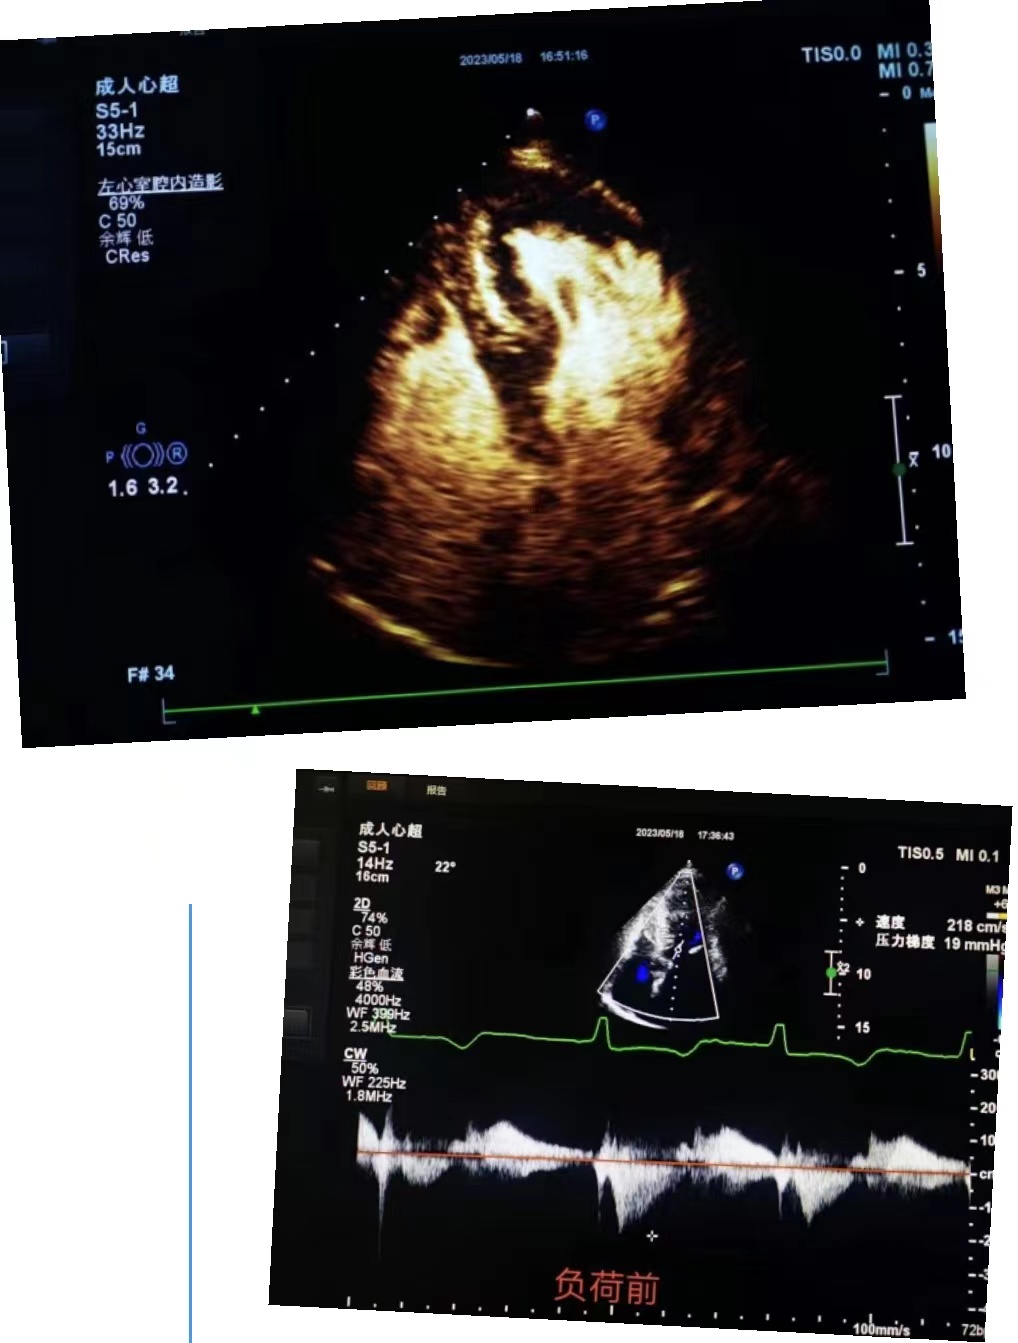

超聲科王英莉主任及心血管組賈貝主治醫師、陳輝主管護師及牛丹青護師為該患者行藥物負荷超聲心動圖。監護儀、急救車到位,常規經胸超聲心動圖提示室間隔增厚,左室流出道血流速度略增快,左心腔超聲造影,可清晰顯示室壁顯著增厚,符合肥厚型心肌病表現,隨后又進行了多巴酚丁胺負荷超聲心動圖,靜息狀態下顯示左室流出道血流速度V:207cm/s,PG:17mmHg;3分鐘后心率達75次/分,左室流出道血流速度V:218cm/s,PG:19mmHg;6分鐘后心率達94次/分,左室流出道血流速度V:386cm/s,PG:60mmHg;9分鐘后達到目標心率,左室流出道血流速度V:649cm/s,PG:169mmHg,停止用藥,藥物負荷試驗陽性,檢查過程中患者無不適癥狀,最終診斷為隱匿性肥厚型梗阻性心肌病。